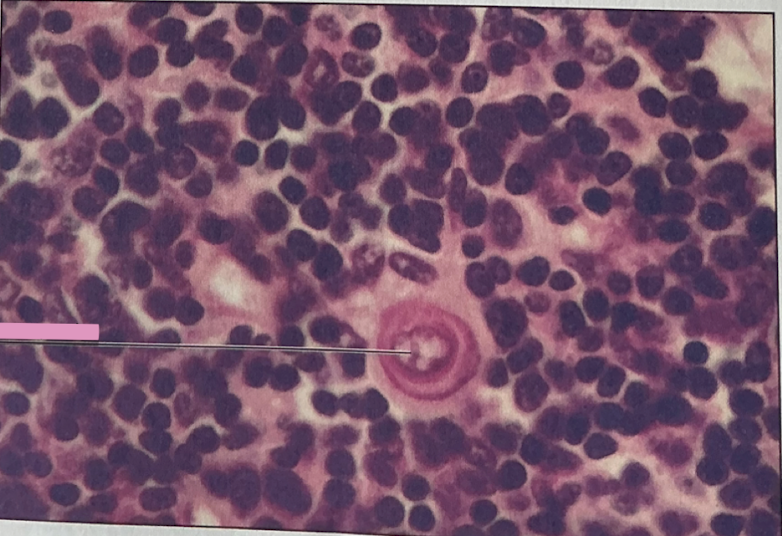

hodgkin’s granuloma

hodgkin’s granuloma

cancer of lymph system - breakdown of red and white pulp

reed-sternberg cells

derived from B lymphocytes